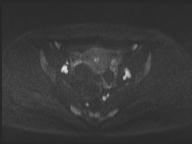

轴位

T2加权像

DWI

此外,肿瘤还累及宫旁组织。影像学检查发现异常淋巴结肿大,最大短轴直径(SAD)为10 mm,位于髂总血管分叉处和髂内动脉链下方。该淋巴结肿大在弥散加权成像(DWI)上显示水限制,且增强扫描后可见强化。